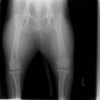

左後肢の挙上を主訴に来院されました。触診にて両関節の前方引き出し兆候、両膝蓋骨の内方脱臼を認めました。関節液検査より免疫介在性多発性関節炎は否定的でした。レントゲン検査にてfat pad signを伴う関節炎が認められたことから、前十字靭帯断裂と膝蓋骨内方脱臼(左GradeⅢ 右GradeⅢ〜IV)併発と診断し、手術を行いました。

術前正面像

術前のTPAは左後肢33.1°右後肢26.8°でしたがTPLO実施により左後肢5.5°右後肢12°に矯正されました。